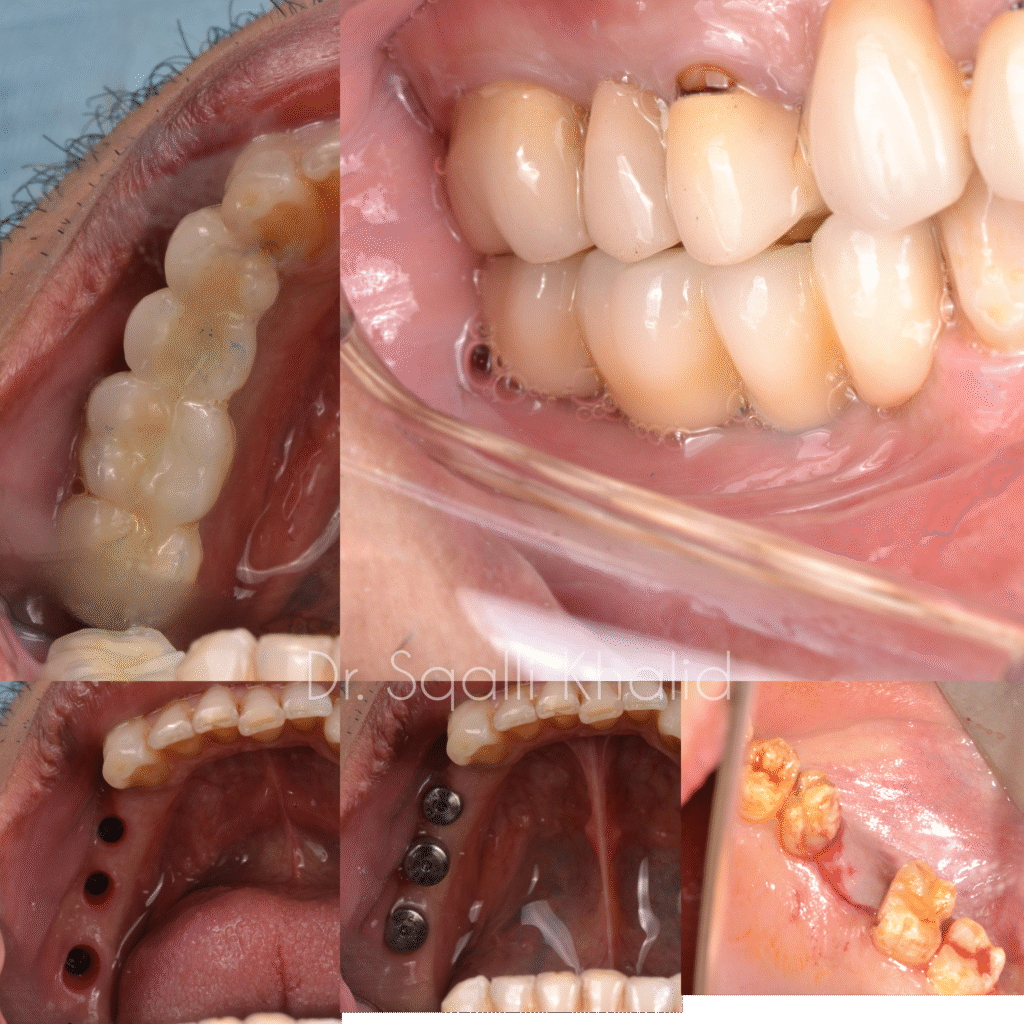

Un implant dentaire est une racine dentaire artificielle en titane biocompatible. Il est placé chirurgicalement dans l’os de la mâchoire et sert de base solide à une couronne, un pont ou même une prothèse complète.

Contrairement aux options traditionnelles telles que les prothèses amovibles ou les bridges, les implants sont fixes, stables et offrent la même sensation que les dents naturelles.

La plupart des adultes en bonne santé bucco-dentaire et générale sont candidats. Même si vous avez perdu de l’os avec le temps, nous pouvons vous recommander une greffe osseuse pour préparer la pose d’implants. Une consultation personnalisée est le meilleur moyen de déterminer votre éligibilité.

Grâce à la planification numérique, à l’imagerie 3D et aux guides chirurgicaux, le processus est aujourd’hui plus rapide et plus prévisible que jamais.